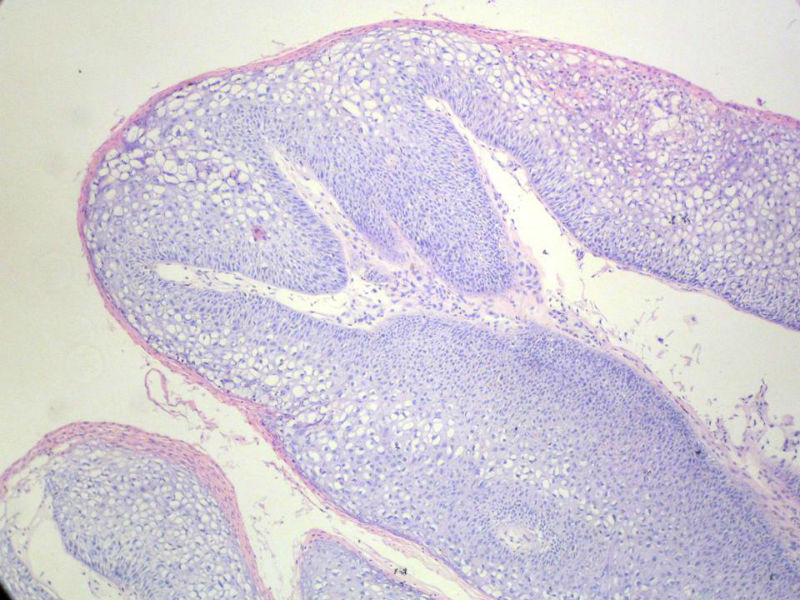

男,72岁,右耳听力下降两个月,检查右外耳道有黄豆大肿物,表面乳头状,手术切除。

乳头状瘤

乳头状瘤,有轻度异形,有恶变倾向

乳头状瘤,上皮内可见挖空样细胞,建议HPV检测